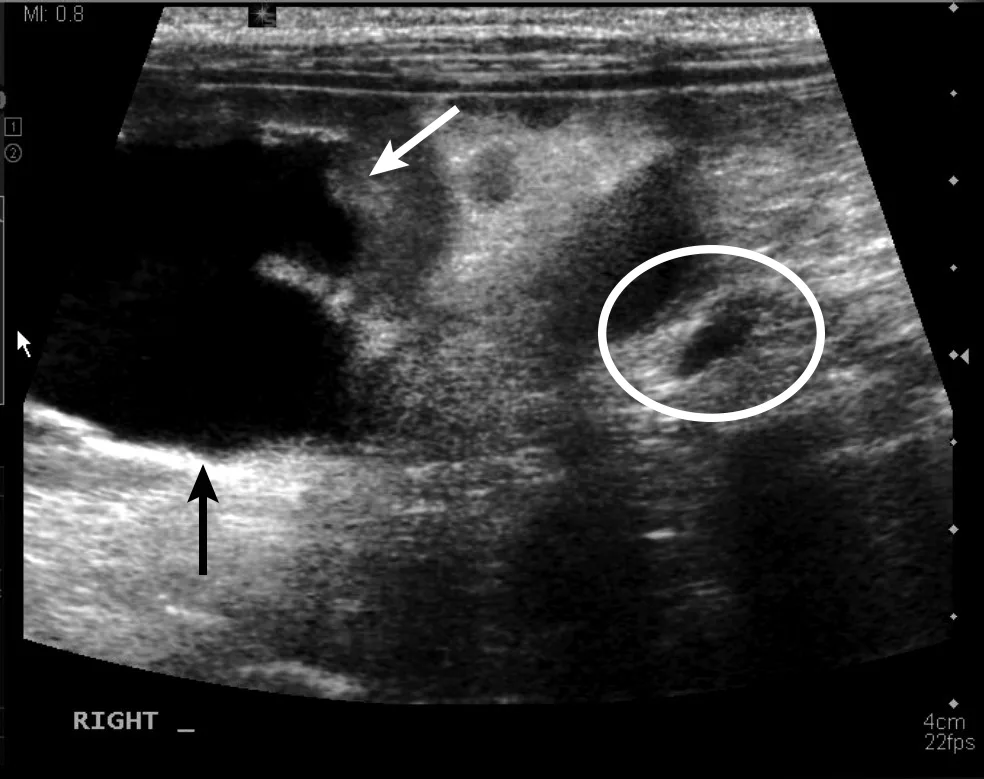

Urinary bladder masses (generally transitional cell carcinoma [Figure 5], but adenocarcinoma or rhabdomyosarcoma are also possible7-9) can cause hematuria or stranguria. On ultrasound, these masses are typically luminal and multilobulated, with rhabdomyosarcoma having a grapelike (ie, botryoid) appearance.7,9 Mineralized urinary bladder masses (rare) are usually urethral transitional cell carcinoma or prostatic adenocarcinoma that locally spreads into the urinary bladder. These masses can occupy the trigone region and occlude the ureters, causing secondary hydronephrosis (Figure 6).8

Sagittal image of the caudal aspect of the right kidney, showing severe dilation of the renal pelvis (arrows) and dilation of the ureter (circle) just caudal to the kidney caused by the transitional cell carcinoma seen in Figure 5. Left, cranial; bottom, dorsal